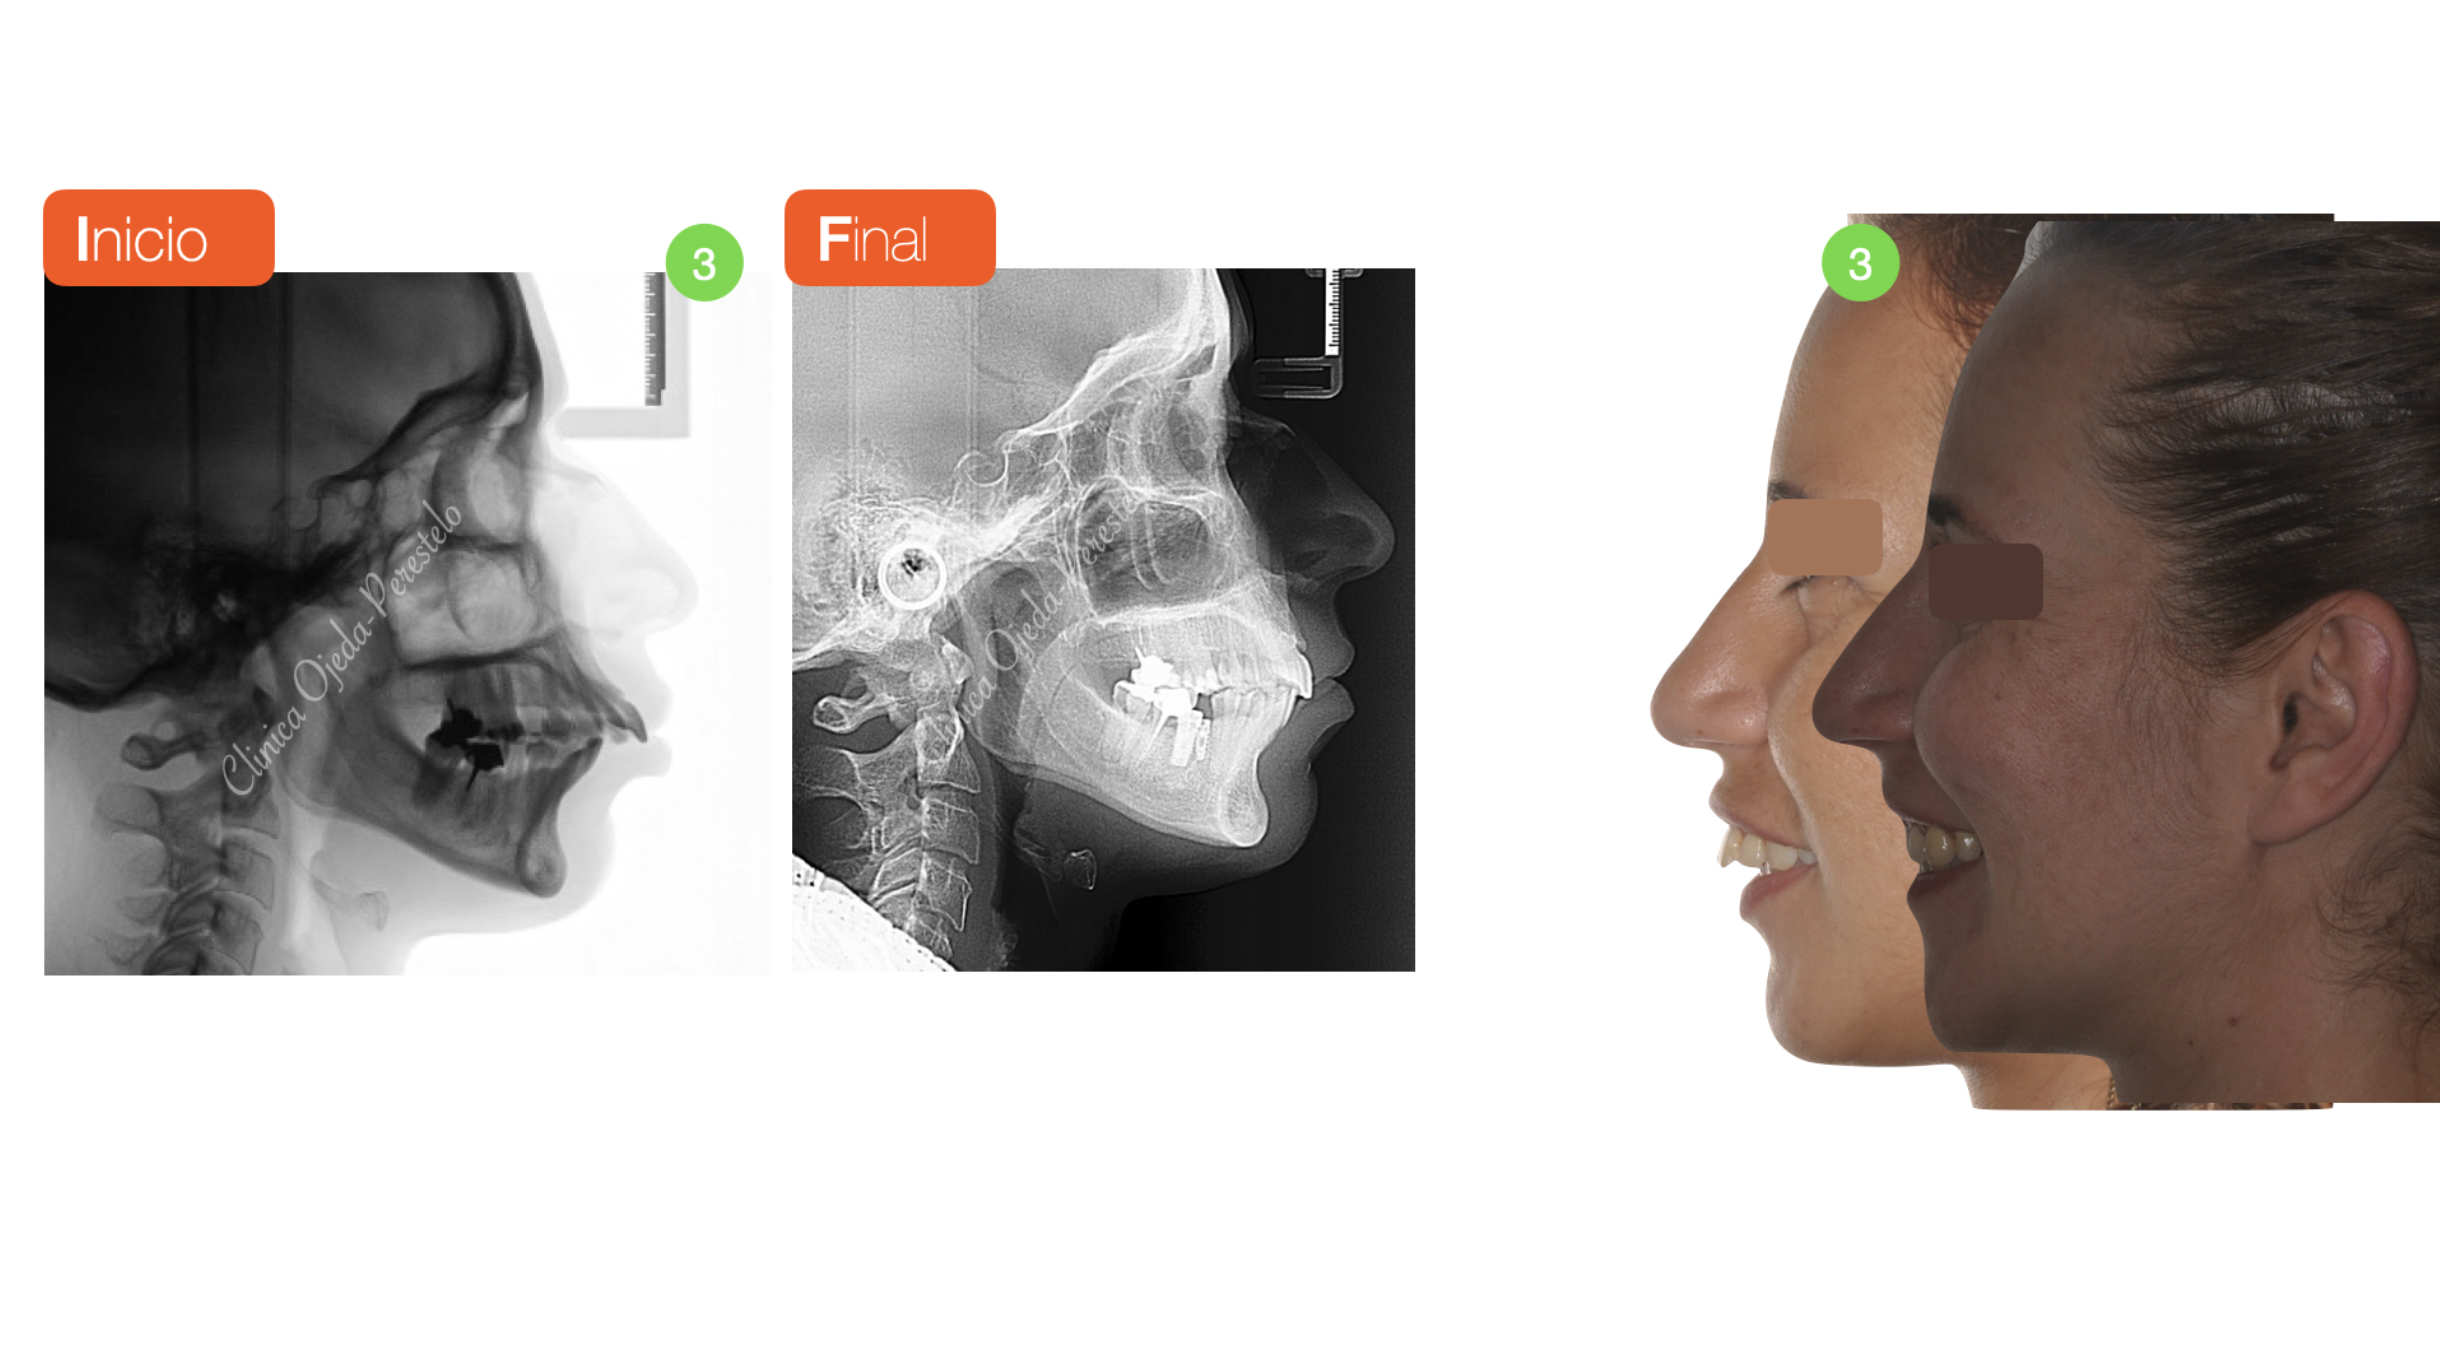

Clase II ósea con Resalte muy Aumentado y Extracciones dentarias

Paciente tratado con brackets de autoligado pasivo (Sistema Damon) donde hemos alineado, nivelado y expandido las arcadas. Además hemos realizado las extracción del primer premolar superior izquierdo ( ya la paciente presentaba extracciones de las piezas 25,45,36 ) para solucionar el gran Resalte presente. La paciente no quería realizarse cirugía ortognática.

Quisieramos destacar cómo las extracciones de premolares no necesariamente comprimen la arcada ni empeoran la amplitud de la sonrisa. La paciente se encuentra en la actualidad pendiente de colocarse sus coronas sobre implantes.